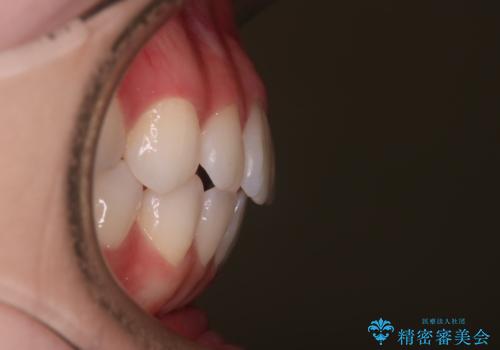

- 前歯の捻転とかみ合わせを主訴に来院されました。今回は抜歯をせずにIPRを実施し、並べる計画を立てました。

ワイヤー矯正を行いながら、顎間ゴムを患者さまにご協力していただき、短い期間で終了できました。